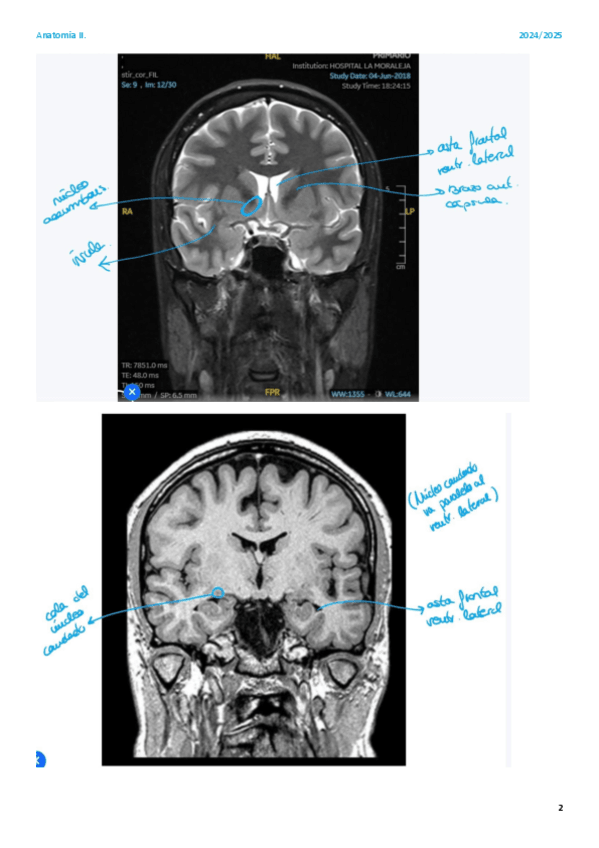

He publicado nuevos apuntes de 2º Anatomía Humana II: practicas-neuroanatomia.pdf

He publicado nuevos apuntes de 2º Anatomía Humana II: practicas-imagenes-resonancias.pdf